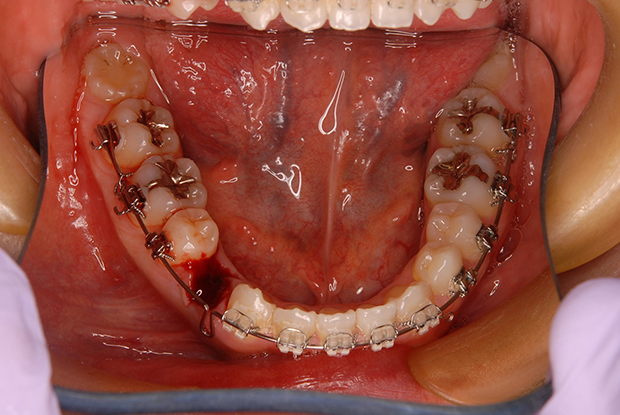

【叢生】抜歯 表側マルチブラケット装置

| 主訴 |

ガタガタ、上の歯が裏側に入っている |

||

|---|---|---|---|

| 診断名 |

左側側切歯crossbiteを伴うAngle I級上下顎前突 |

||

| 年齢 | 21歳 | 性別 | 女性 |

| 治療に用 いた装置 |

唇側マルチブラケット装置 (メタルワイヤー) | 抜歯部位 | 上下顎両側第一小臼歯 |

| 治療期間 ・回数 |

2年6か月・30回 | 治療費 概算 |

約75万円 (調整料を含む) |

| 治療内容 詳細 |

表側のマルチブラケット装置で治療した典型的な抜歯症例です。抜歯したスペースを利用して前歯を後退させ、ガタガタを解いています。 |

||

| リスク・ 副作用 |

装置による違和感。疼痛など |

||